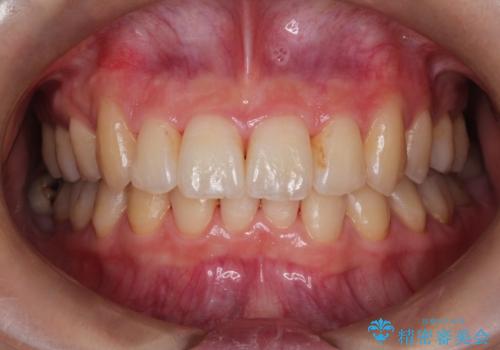

- 前歯の見た目の改善を希望され来院された患者様です。

見た目、嚙み合わせ及び、治療期間や施術内容に大変ご満足いただきました。